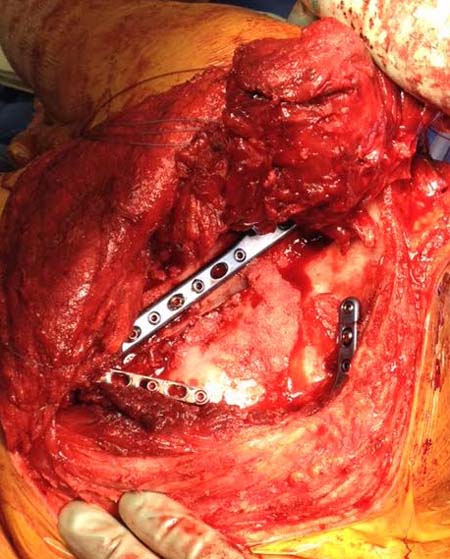

Здесь пример, стандартные снимки: плечо и лопатка прямой снимок, аксиллярный и косой снимки (Y-view) и фиксация пластинами по краям, где имеется более твердая кость. Специальные пластины, хотя любая 2.7 или 3.5 мм тубулярная пластина подойдут для фиксации перелома. Риск операции - это повреждение нерва во время доступа и ре-фиксация ротаторной манжетки если потребуется широкий доступ!

Данный перелом относится к перелому тело лопатки и несмотря на наслоение, где лопатка покрывает грудную клетку, но можно увидеть три большие фрагмента, которые находятся в разных плоскостях. Суставная поверхность расположена намного медиальнее, что нарушает бланс мышц, которая в последующем может привести к ограничению движения верхного пояса. Расположение суставной поверхности нуждается в уточнении дополнительными исследованиями, включая КТ и стандартные снимки плеча.!